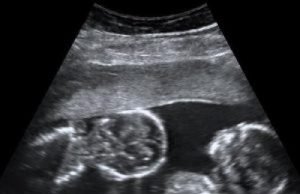

Twins and Breech Babies: Human Birth, Part 4

In this comprehensive series of normal labor and delivery off the grid, we’ve discussed late-term pregnancy, the signs of impending labor, the progress through...